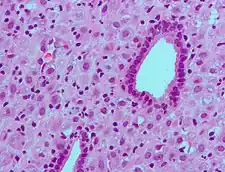

- Histopathology Uterus – Decidual reaction Microscopic review of decidualization